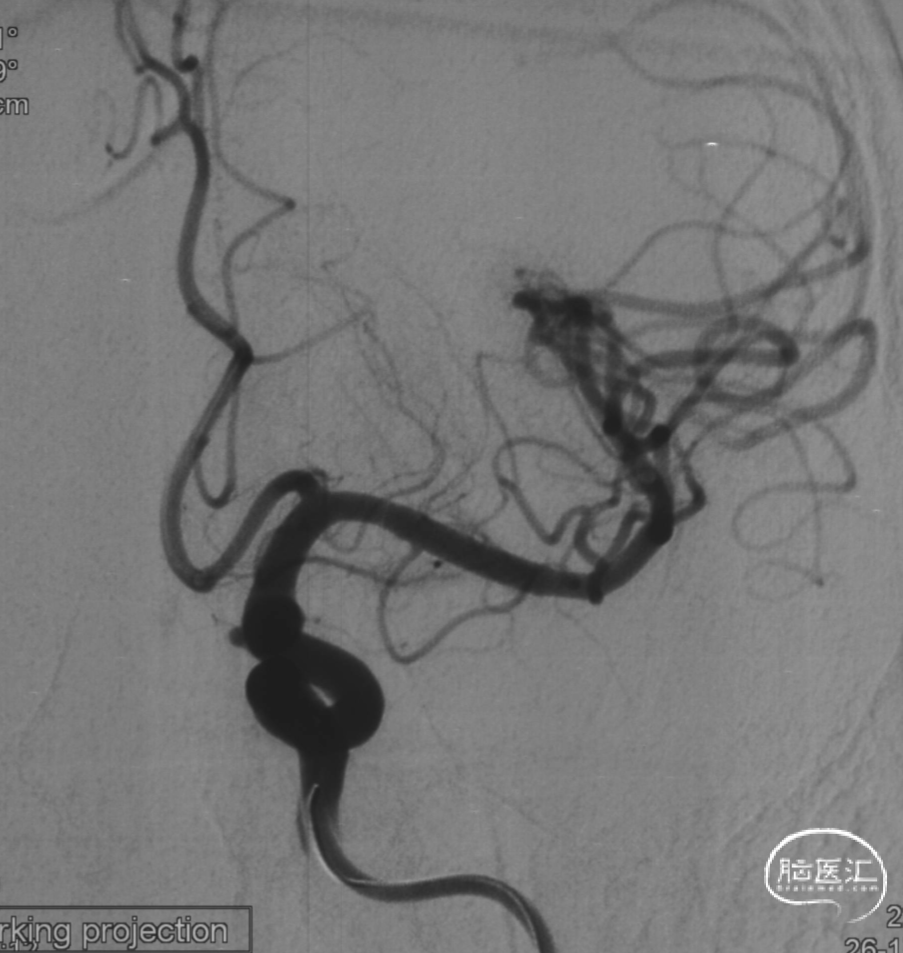

经桡动脉入路左侧颈内动脉通路建立

可见一小泡自动脉瘤瘤体上发出

同侧A1可见一小瘤突起

选择工作角度